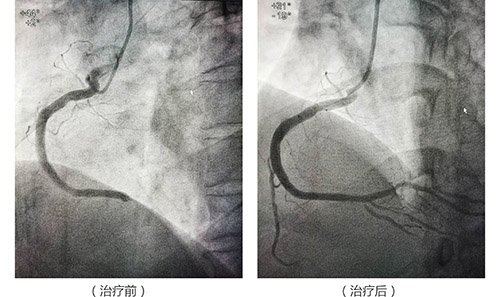

【案例】急性胸痛保心治疗

38岁男性,胸痛2小时来诊,心电图示急性下壁ST段抬高心肌梗死……

心内科立即组织抢救,介入小组迅速反应,谈伍平医生(副主任医师),范春林医师,陈家丽护师配合默契,在90分钟内完成了冠脉造影,球囊扩张+支架植入,又一个患者的心脏保治疗成功完成。